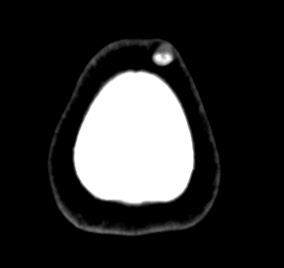

Клинически пиломатриксома представляет собой узел шаровидной или шальной формы, хорошо пальпируемый под поверхностью кожи. Характерная особенность этой опухоли - ее плотная консистенция. Опухоль не спаяна с окружающими тканями, подвижна, иногда умеренно болезненна при пальпации. Обычный размер новообразования 0,5-3 см и более. В начале заболевания расположенный в глубоких слоях кожи опухолевый очаг больших размеров практически не заметен и не вызывает никаких субъективных ощущений у пациента. С течением времени, постепенно увеличиваясь в размepax, опухоль начинает выбухать над поверхностью кожи, которая иногда выглядит истонченной, атрофичной, гиперемированной, может шелушиться и порываться коркой (изредка встречаются пигментные формы). Больные начинают предъявлять жалобы на гуд, жжение, покалывание и (чаще всего при локализации на лице) на онемение.

Гистологическое строение злокачественной пиломатриксомы. Эпидермис над опухолью не имеет характерных особенностей, истончен или изъязвлен. Подобно своему доброкачественному аналогу, опухоль содержит базалоидные клетки и клетки-тени. Базалоидные клетки располагаются по периферии тяжей и островков, инфильтрирующих окружающую строму. В центре эпителиальных комплексов находятся клетки-тени с эозинофильной цитоплазмой и остатком бледног ядра. Отмечается переходная дифференцировка в плоские клетки и светлые клетки без атипии. Могут также формироваться кистозные полости. Как и при пиломатриксоме, в злокачественной пиломатриксоме определяются кератинизация. кальцификация. Строма фиброзная, содержит очаговые скопления гистиоцитов и гигантских многоядерных клеток инородных тел.